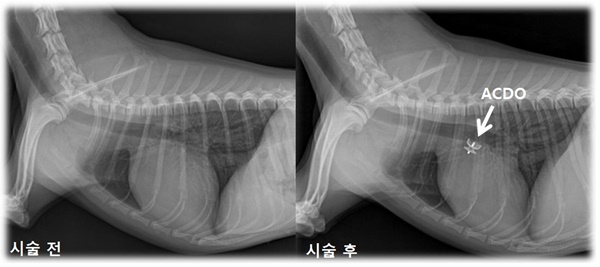

박희명 수의대 교수팀은 지난달말 동맥관개존증(PDA)을 가진 환견에게 Amplatz® Canine Duct Occluder(ACDO)를 이용한 폐쇄술을 약 30분만의 국내 최단 시간으로 성공했다. 이는 미국의 심장전문의 시술 시간보다(평균 2시간) 훨씬 짧고 특히 소형견에서의 시술로서는 매우 빠른 것이다.

동맥관개존증 폐쇄술은 가느다란 관을 사타구니 쪽의 작은 혈관을 이용해 심장까지 밀어넣은 후 동맥관 폐쇄기구를 삽입하는 시술로, 평균 시술 시간이 2시간 정도이며 시술 이후 고통이 적고 회복이 빨라 시술 1일 이내에 퇴원이 가능하다.